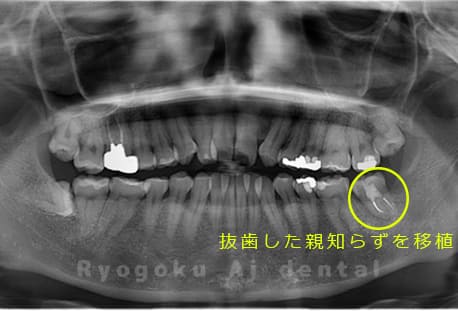

Case14

- 重度カリエス、親知らず

- 治療内容

- 親知らずの抜歯、移植手術、マイクロエンド、ダイレクトボンディング

- 治療費用

- 220,000円

他院で親知らずと共に抜歯と診断された患者様です。親知らずの抜歯の必要性と左下奥歯の保存を試みた場合、歯の状態から根管治療、歯周外科、補綴の必要性から、移植治療を選択されました。大きな問題もなく、治療後も経過良好です。

<リスク・副作用>

治療後、痛みや違和感、出血、腫れなどが出る事があります。喫煙者、糖尿病などの方の場合、歯が生着しない場合があります。